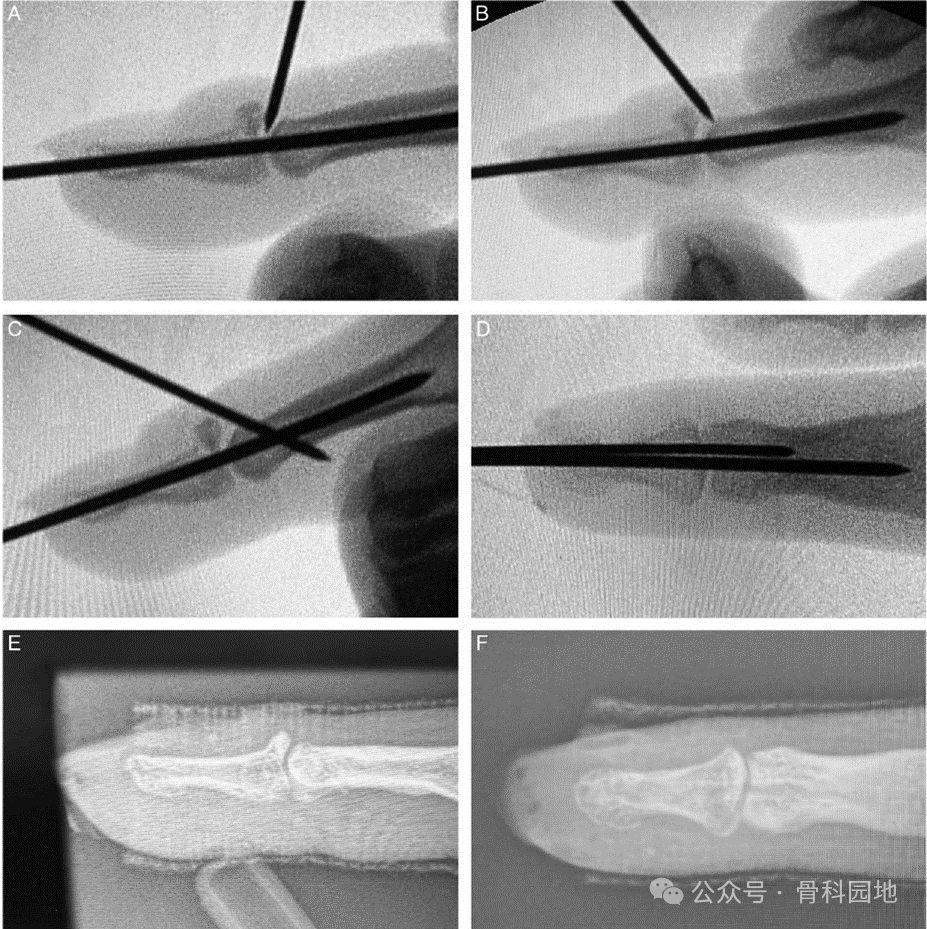

1、复位时,应避免对指尖施加压力,避免过伸,适当的复位是通过对指骨底部施加压力来实现的(图)。

2、为了解决软组织嵌入骨折间隙,可以通过施加牵引力和背推指骨基底,“挤奶”的动作(图)。

3、当背侧骨块难以用单一的背侧克氏针复位时,可以使用2根直径较小的克氏针,以便更好更强地操纵(图)。

4、如果两个骨折块不能闭合复位,通常发生在伤后3- 5周,建议用一根针头从手指背部插入骨折间隙复位,并经皮轻轻刮擦复位部位。克氏针也可以用于这种操作,但克氏针在这些情况下不如针有效,因为针尖有锋利的切割边缘(图)。

5、当克氏针施加的压力使背侧骨块复位,但不动时复位失去一部分,可能有必要通过捆绑背侧和对背侧骨块施加永久压迫力。橡皮筋固定(图)